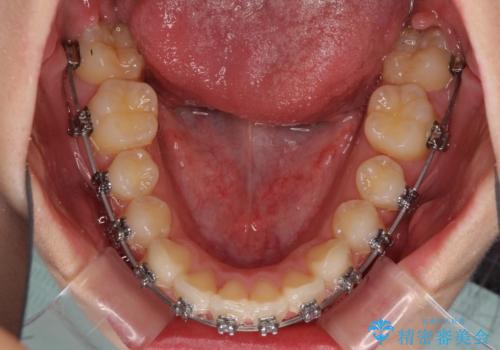

- メタルブラケット

左右ともに上顎奥歯が外を向き、下顎奥歯が内側に倒れているシザーズバイトであったため、補助装置により改善することとしました。

左側の咬み合わせと上下正中の位置をコントロールするために時間がかかりましたが、事前に思い描いた通りの歯列に整い、患者様には大変満足していただきました。